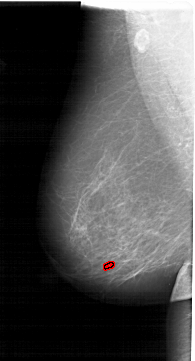

A_1513_1.LEFT_MLO

LEFT_MLO LINES 6496 PIXELS_PER_LINE 3496 BITS_PER_PIXEL 12 RESOLUTION 43.5 OVERLAY

FILE: A_1513_1.LEFT_MLO.OVERLAY

TOTAL_ABNORMALITIES 1

ABNORMALITY 1

LESION_TYPE CALCIFICATION TYPE PLEOMORPHIC DISTRIBUTION CLUSTERED

ASSESSMENT 4

SUBTLETY 1

PATHOLOGY BENIGN

TOTAL_OUTLINES 1

BOUNDARY